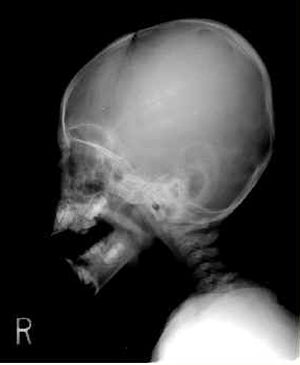

X-선 소견

두개관에 골경화상 인지

전두골화 두정골에 많이 발생

경계가 확실하지 않은 0.2~2cm크기의 농도가 짙은 영역으로 인지